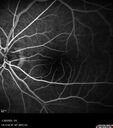

Recurrent toxoplasmosis with elevated IOP33 views48 year old man with 4 episodes over 40 years of vision loss from toxoplasmosis. His IOP was 44 on presentation.

Recurrent toxoplasmosis with elevated IOP30 views48 year old man with 4 episodes over 40 years of vision loss from toxoplasmosis. His IOP was 44 on presentation.

Recurrent toxoplasmosis with elevated IOP27 views48 year old man with 4 episodes over 40 years of vision loss from toxoplasmosis. His IOP was 44 on presentation.

Recurrent toxoplasmosis with elevated IOP26 views48 year old man with 4 episodes over 40 years of vision loss from toxoplasmosis. His IOP was 44 on presentation.